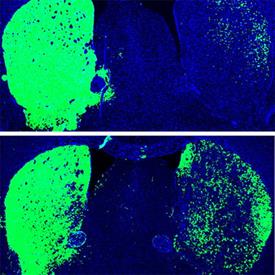

Inevitabile l’applicazione di questa scoperta alla ricerca sulle malattie neurodegenerative, Parkinson in particolare. Il trattamento di inibizione della PTB nei topi ha portato alla conversione degli astrociti, cellule cerebrali di supporto, in nuovi neuroni in grado di produrre dopamina. Con questo trattamento, i topi affetti da Parkinson hanno mostrato una completa remissione dei sintomi, senza alcuna recidiva a distanza di tempo. I risultati della ricerca sono stati pubblicati sulla prestigiosa rivista Nature in data 24 giugno.

Il trattamento viene effettuato inoculando un virus non infettivo che trasporta una sequenza oligonucleotidica, cioè una sequenza di DNA generata artificialmente per legarsi all’RNA che codifica la PTB. In questo modo la sezione di RNA che dovrebbe generare la proteina non è più in grado di farlo, e lo sviluppo di nuovi neuroni può svolgersi con più facilità. Nei topi sottoposti a trattamento, il numero di neuroni è aumentato di circa il 30% e i livelli di dopamina hanno raggiunto la soglia della normalità.